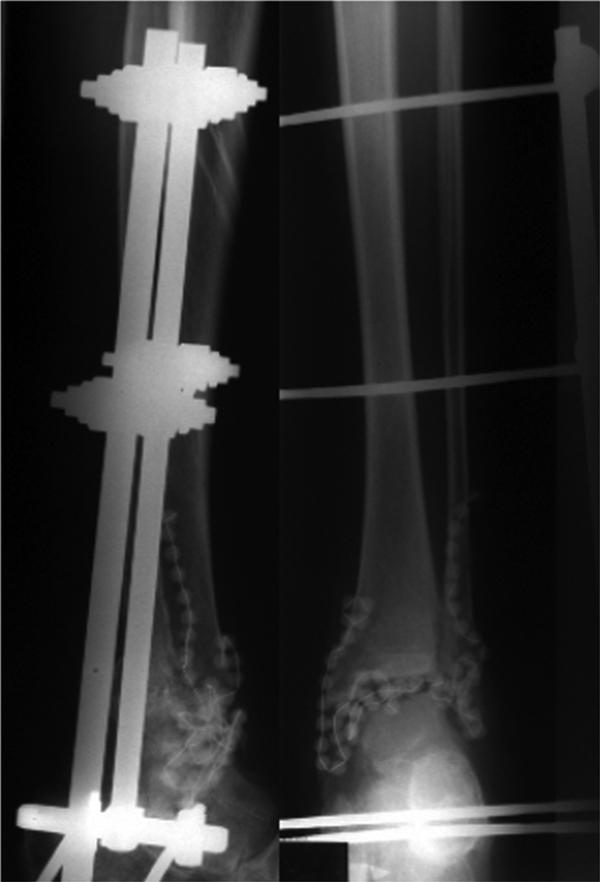

Although there is a clear trend toward internal fixation for ankle arthrodesis, there is general consensus that external fixation is required for cases of posttraumatic infection. We retrospectively evaluated the technique and clinical long term results of external fixation in a triangular frame for cases of posttraumatic infection of the ankle. From 1993 to 2006 a consecutive series of 155 patients with an infection of the ankle was included in our study. 133 cases of the advanced "Gächter" stage III and IV were treated with arthrodesis. We treated the patients with a two step treatment plan. After radical debridement and sequestrectomy the malleoli and the joint surfaces were resected. An AO fixator was applied with two Steinmann-nails inserted in the tibia and in the calcaneus and the gap was temporary filled with gentamicin beads as the first step. In the second step we performed an autologous bone graft after a period of four weeks. The case notes were evaluated regarding trauma history, medical complaints, further injuries and illnesses, walking and pain status and occupational issues. Mean age at the index procedure was 49.7 years (18-82), 104 patients were male (67.1%). Follow up examination after mean 4.5 years included a standardised questionnaire and a clinical examination including the criteria of the AOFAS-Score and radiographs. 92.7% of the cases lead to a stable arthrodesis. In 5 patients the arthrodesis was found partly-stable. In six patients (4,5%) the infection was not controllable during the treatment process. These patients had to be treated with a below knee amputation. The mean AOFAS score at follow up was 63.7 (53-92). Overall there is a high degree of remaining disability. The complication rate and the reduced patient comfort reserve this method mainly for infection. Joint salvage is possible in the majority of cases with an earlier stage I and II infection.

虽然踝关节融合术的内固定有明显的趋势,但普遍认为,对于创伤后感染的病例,需要外固定。我们回顾性评估了三角架外固定治疗踝关节创伤后感染的技术和临床长期结果。1993 年至 2006 年,我们连续收治了 155 例踝关节感染患者。其中 133 例为晚期“Gächter”III 期和 IV 期患者行融合术治疗。我们采用两步治疗方案治疗患者。彻底清创和病灶清除后,切除内外踝和关节面。首先应用 AO 固定器,胫骨和跟骨各插入两根斯氏针,临时用庆大霉素珠填充间隙。4 周后进行自体植骨。通过病历评估创伤史、医疗投诉、进一步的损伤和疾病、行走和疼痛状况以及职业问题。指数手术时的平均年龄为 49.7 岁(18-82 岁),104 例为男性(67.1%)。平均 4.5 年后的随访检查包括标准问卷和临床检查,包括 AOFAS 评分和 X 线标准。92.7%的病例融合稳定。5 例融合部分稳定。6 例(4.5%)患者在治疗过程中感染无法控制。这些患者需要进行膝下截肢。随访时的平均 AOFAS 评分为 63.7(53-92)。总体上仍有高度的残疾。并发症发生率和降低的患者舒适度使这种方法主要适用于感染。对于早期 I 期和 II 期感染,大多数病例都可以进行关节挽救。